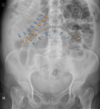

Where should the X-ray cover in an abdominal X-ray?

- pubis bone up to diaphragm

- ilias of hips

In an abdominal X-ray should patients inhale or exhale on an X-ray?

- image is captured during exhalation

What are a few of the anatomical landmarks that need to be included on an abdominal X-ray?

- diaphragm

- L4 vertebral body

- iliac crest

- left and right flanks

- sacrum and superior pubic ramus